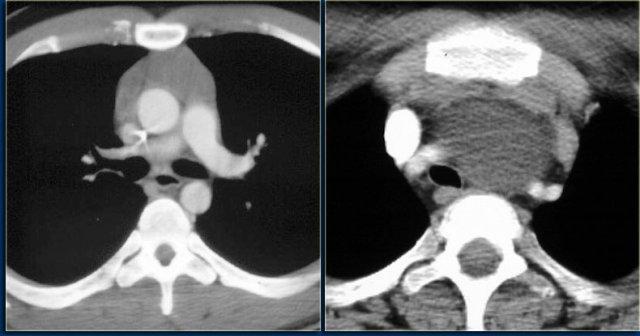

Các hình ảnh CT cho thấy một khối vôi hóa ở trung thất sau trải dài qua nhiều đốt sống, xâm lấn vào ống sống.

Trên các hình ảnh MRI, sự xâm lấn vào ống sống được thể hiện rõ hơn (các mũi tên).

U nguyên bào thần kinh thường có hình thoi, tỷ trọng mô mềm; 50% các khối u lồng ngực có vôi hóa.

U nguyên bào thần kinh phát triển qua nhiều khoang liên sườn và thường xâm lấn ống sống.